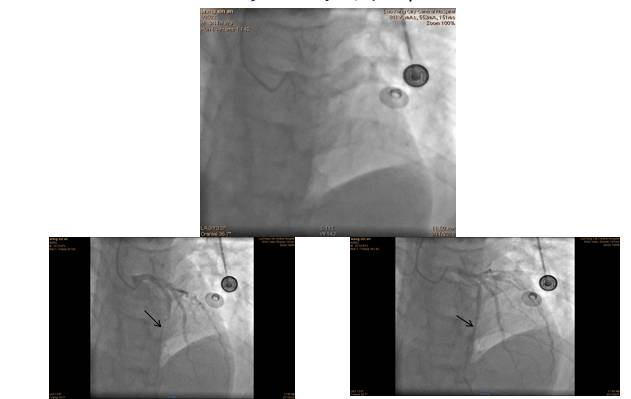

◆2016年3月15日冠状动脉造影示:前降支远段心肌桥,收缩时90%狭窄。

影像学资料